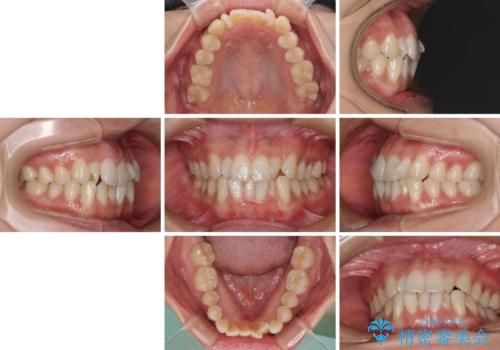

捻れた前歯をできるだけ短期間で 表側のワイヤー矯正

- 上下前歯のねじれを気にして来院された患者様です。

ワイヤー矯正でもマウスピース矯正でも対応可能でしたが、マウスピース矯正の自己管理が面倒であること、上顎前歯の捻転が著しいことから、ワイヤー矯正での治療を希望されました。

日々前歯の捻れが解消されていくので、歯の動きを楽しみながら矯正治療を進めることができました。